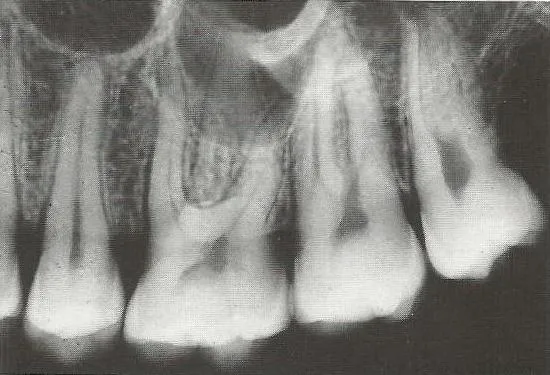

Zdjęcie punktowe, zwane również zdjęciem zębowym, to podstawowe i najczęściej wykonywane badanie rentgenowskie w diagnostyce bólu. Pozwala mi ono na bardzo szczegółową ocenę jednego lub dwóch zębów. Na takim zdjęciu mogę zobaczyć:

- Stan korzenia zęba i jego anatomii.

- Kość wokół wierzchołka korzenia szukam zmian okołowierzchołkowych, takich jak zapalenia czy torbiele, które są częstą przyczyną bólu.

- Głębokość ubytku próchnicowego, zwłaszcza jeśli jest on ukryty pod wypełnieniem lub w trudno dostępnym miejscu.

- Jakość wcześniejszego leczenia kanałowego, jeśli ząb był już leczony.

To badanie jest niezwykle precyzyjne i często ujawnia problemy, które są całkowicie niewidoczne podczas badania klinicznego.